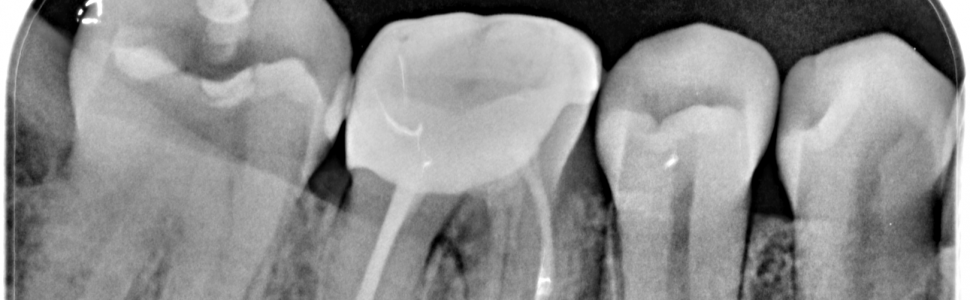

Zabieg hemisekcji polega na usunięciu jednego z korzeni zęba wraz z jego częścią koronową, najczęściej w przypadku zębów trzonowych dolnych. Stanowi alternatywę dla ekstrakcji zęba w przypadku powikłań po leczeniu endodontycznym lub periodontologicznym. W pracy przedstawiono dwa przypadki kliniczne prezentujące przeprowadzone zabiegi hemisekcji. Pierwszy z nich wykonano u pacjenta z próchnicą drążącą wzdłuż korzenia dystalnego poniżej poziomu kości, a drugi u pacjentki z zaostrzoną zmianą okołowierzchołkową przy korzeniu mezjalnym po nieudanej próbie powtórnego leczenia endodontycznego w innym gabinecie.

The hemisection involves removing one of the tooth roots with its coronal portion, most commonly in mandibular molars. It is an alternative to tooth extraction in case of complications after endodontic or periodontal treatment. This paper reports two clinical cases presenting the hemisection procedures. The first one was performed in a patient with caries drifting along the distal root below the bone level, and the second one in a patient with an exacerbated periapical lesion at the mesial root after unsuccessful endodontic retreatment in another dental office.